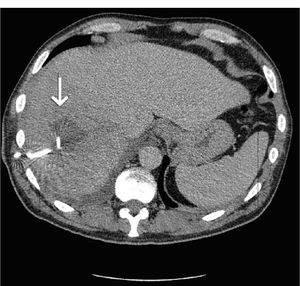

A repeat CT scan was performed eleven days later and showed that the liver abscess had decreased in size to 4 x 3cm (Figure 2). There was though marked left hydronephrosis. A paracolic diverticular abscess was also noted, which was believed to have been the primary source of the liver abscess as well as the cause of ureteric obstruction (Figure 3). Microbiology had confirmed the presence of actinomycosis within the abscess that had been drained.